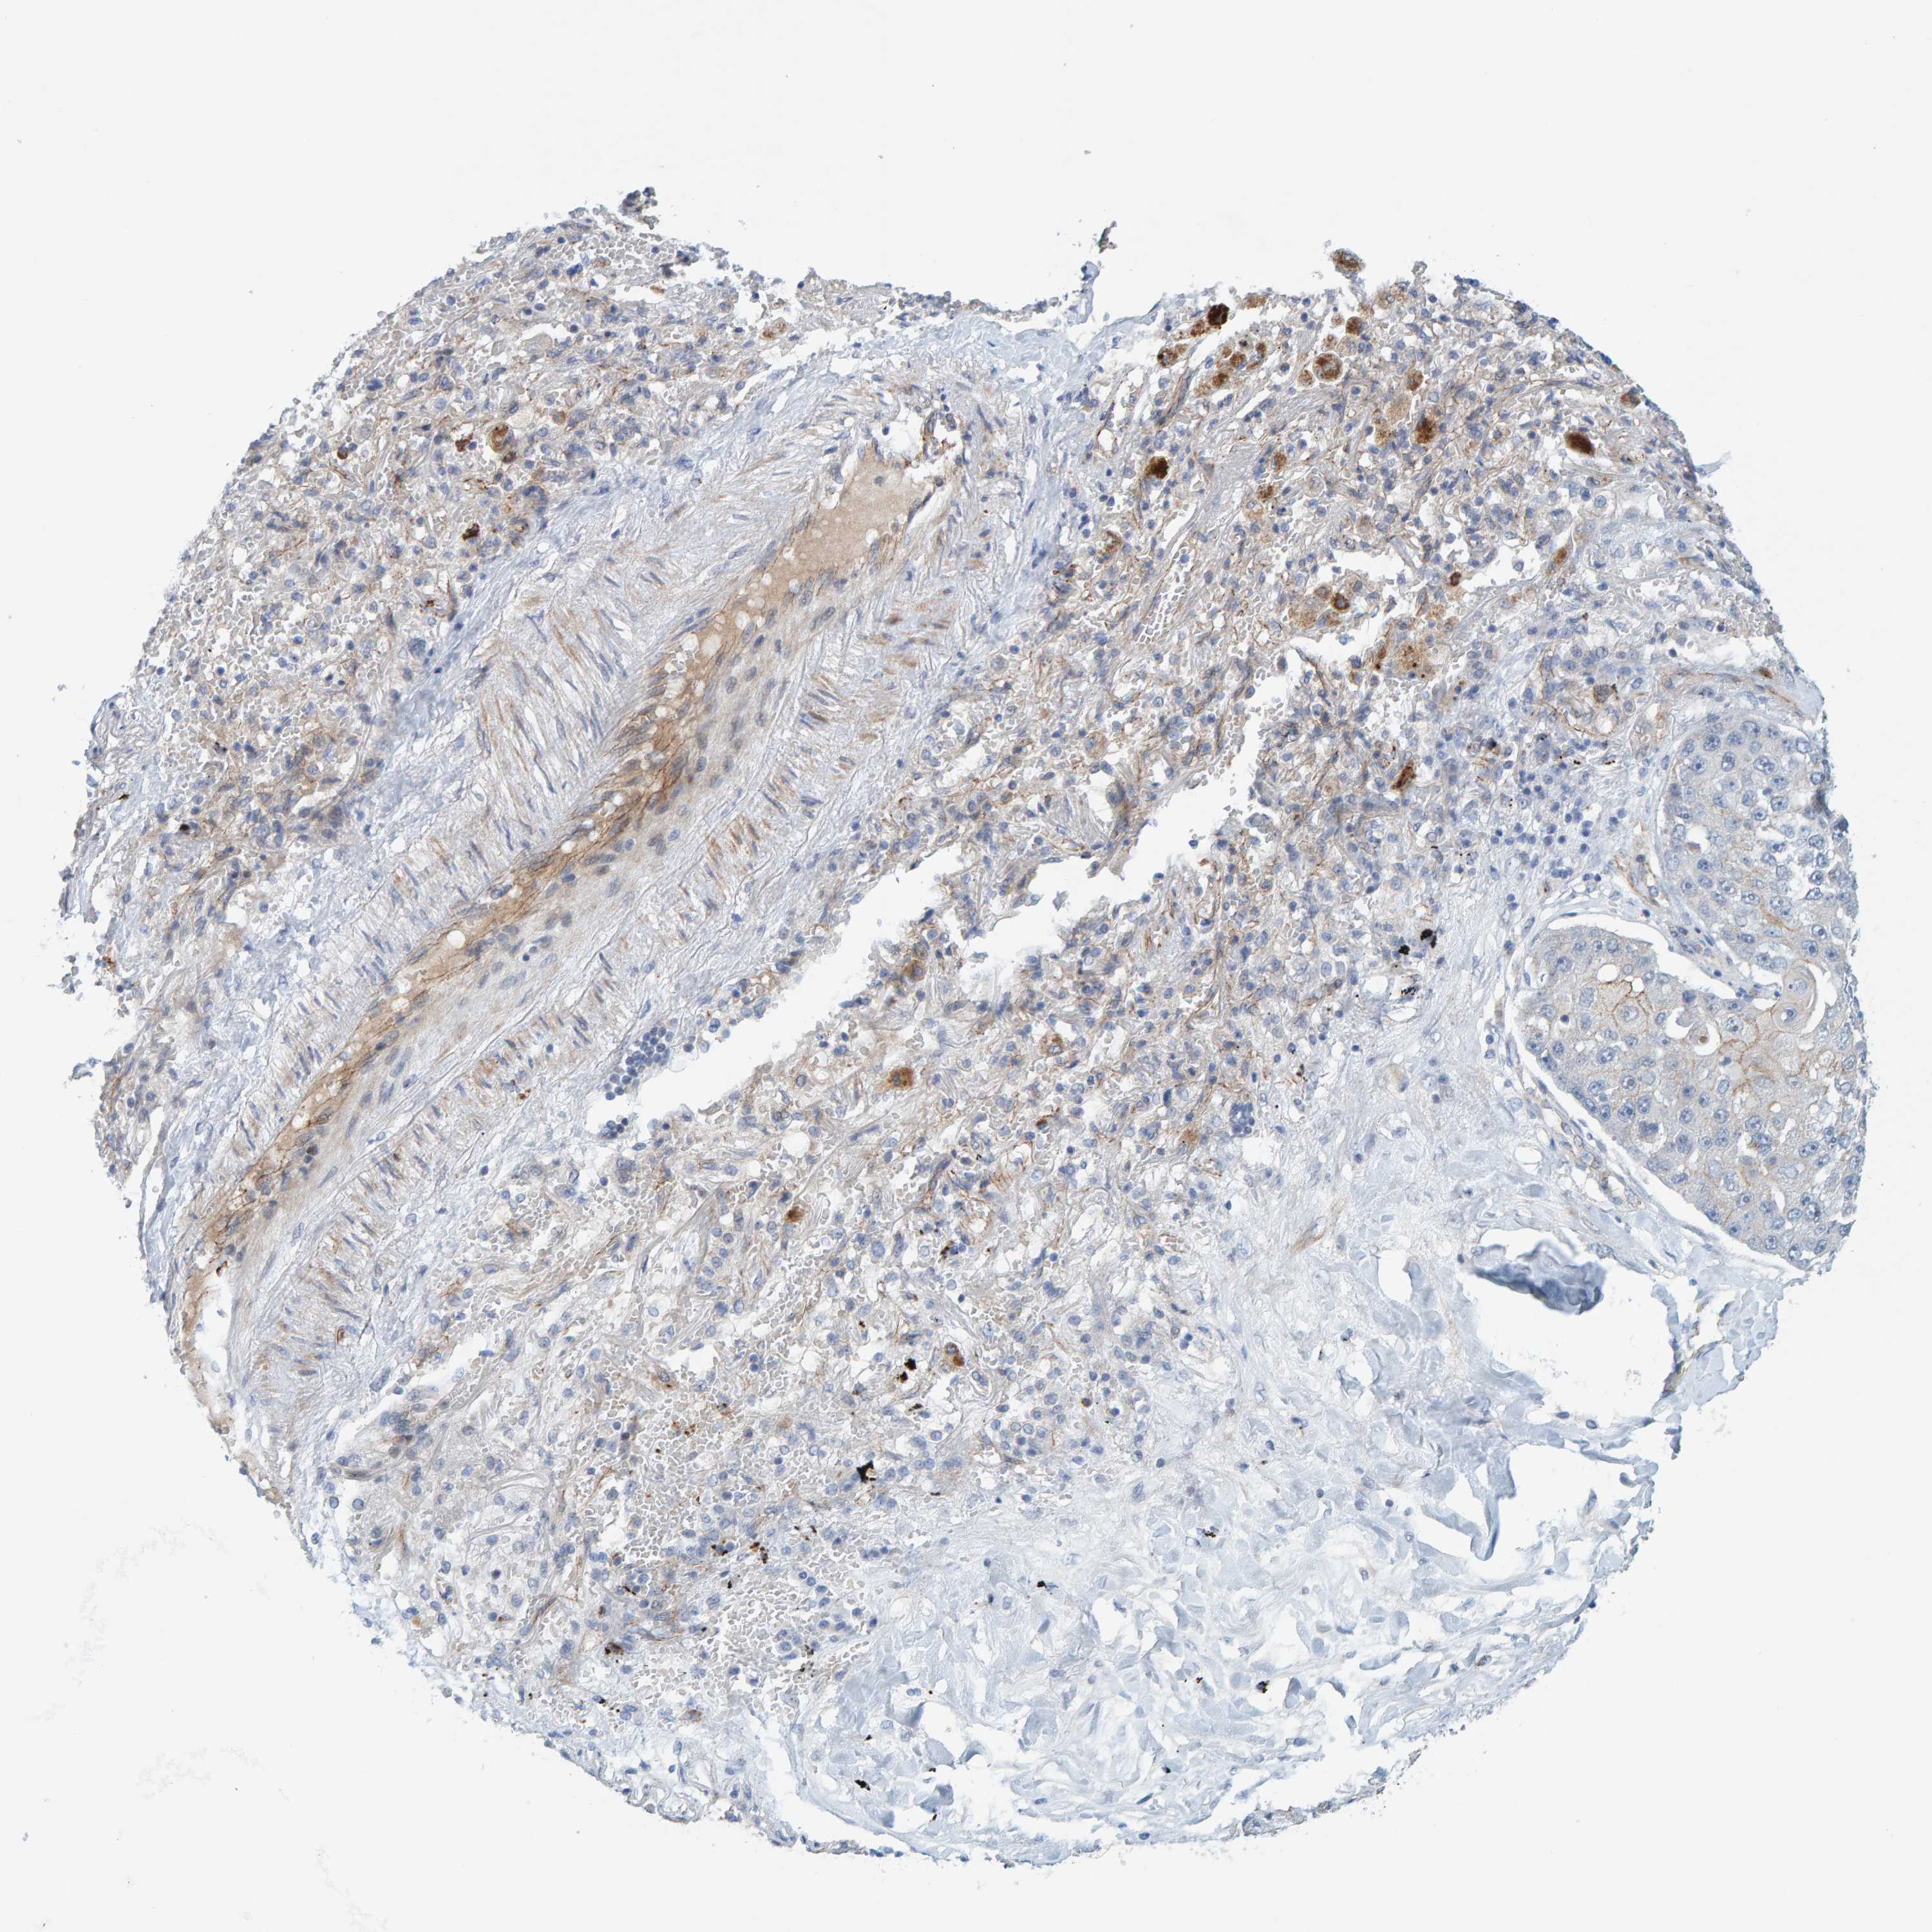

CANCER LUNG CANCER Show tissue menu

LUAD TCGA LUAD VALIDATION LUSC TCGA LUSC VALIDATION PROTEIN LUAD CPTAC PROTEIN LUSC CPTAC PROTEIN EXPRESSION

ANTIBODIES

AND

VALIDATION